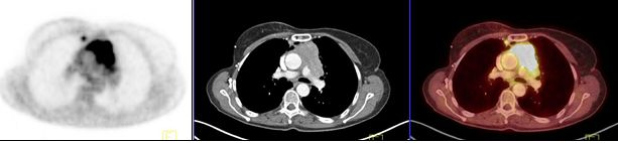

Los carcinomas tímicos (figs. 3, 4 y 5) se destacaron por un elevado metabolismo, con un SUVmax promedio de 10,4 (rango 5,6 a 13,2) y presentaron contornos irregulares, con compromiso de la grasa y de estructuras vecinas, presencia de calcificaciones, parálisis frénica (6 casos en 7) y siembra o derrame pleural o pericárdico (4 casos en 7).